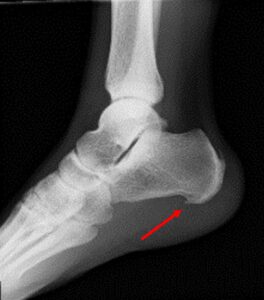

・X線検査:骨棘(かかとの骨の突起)や他の疾患の有無を確認

・MRI検査:難治例や他疾患の鑑別が必要な場合に実施